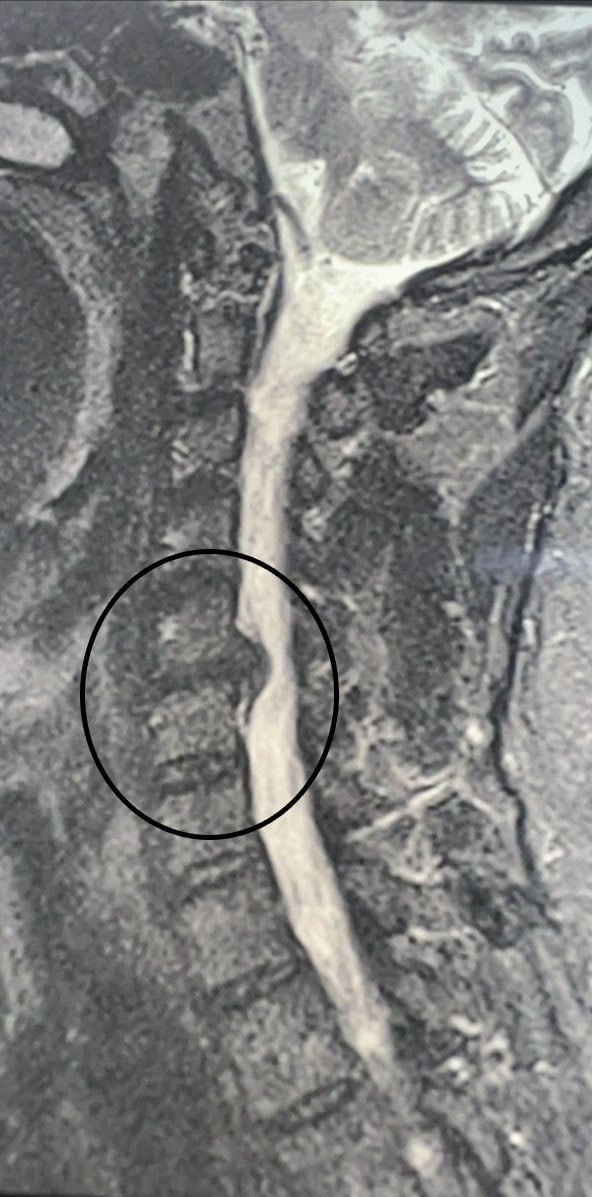

В конце октября в больницу обратился 49-летний мужчина, у которого месяц болела шея. Кроме того, пациент жаловался на онемение и слабость в правой руке. Ранее мужчина проходил лечение, но оно не помогло. Врачи обнаружили грыжу, спондилоартроз и радикулит. Без удаления грыжи у пациента мог развиться паралич правой руки, поэтому было принято решение провести операцию.

Нейрохирурги удалили межпозвонковый диск и грыжу. Помимо этого, была устранена компрессия спинного мозга и нервных корешков, а также установлен межтеловой кейдж – металлическая конструкция, которая размещается между двумя соседними позвонками и соединяет их между собой. Послеоперационный период протекал без осложнений. Уже на следующий день пациенту разрешили вставать и ходить. Через семь дней мужчину выписали.